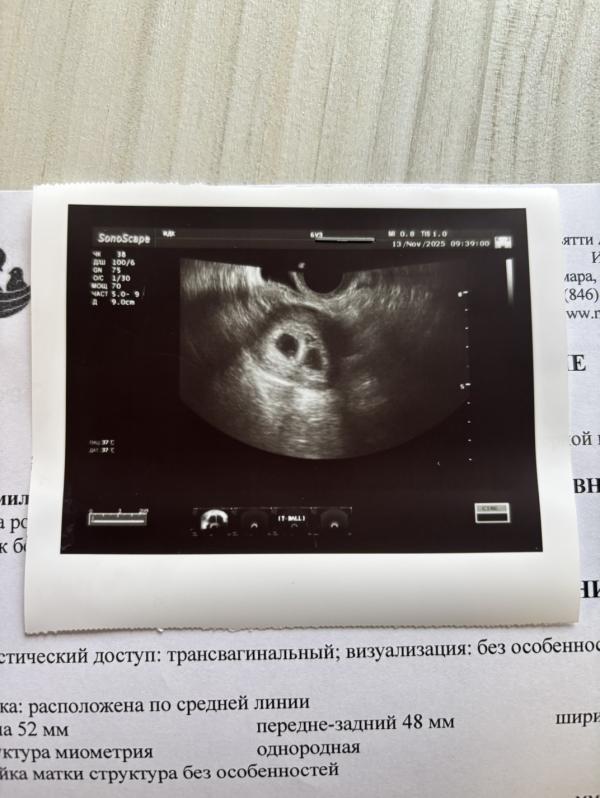

6,1 срок

Сердечко еще не слышно , в следующий раз.

Спасибо. Там целый консилиум собрался из двух врачей перед экраном 😁 сперва «ну нет , один»; потом «ну нет вот же второй» 😁 я думала с ума сойду 🤪 страшно очень , но такое счастье 🥹